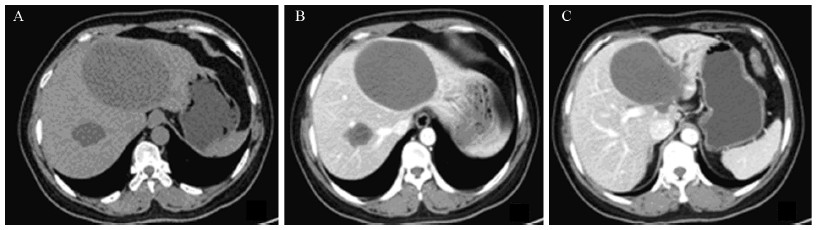

患者于2013年3月21日行CT引导下肝囊肿穿刺引流术,见囊液为暗褐色、无异味黏稠液体。术中及术后囊液多次免疫学检测显示:CA19-9均呈超高水平表达( > 10 000 u/ml)、其中术中留取标本中CA19-9值达15 947 u/ml。引流后间断3次留取囊液行细胞学检查,结果均提示可见变性坏死物,未检测到细菌、肿瘤细胞和寄生虫;CA19-9水平也呈逐渐下降趋势,术后第3天、6天分别为10 813 u/ml、8 784 u/ml。引流一周后复查上腹MRI提示:肝左叶可见10.6 cm×6.8 cm大小异常信号肿物影,T1WI呈不均匀稍高信号、T2WI呈不均匀高信号,边界尚清,增强后未见明显强化、周围胆管轻度扩张,见图 2。血管、胆管受压以及囊液CA19-9超高水平表达不能排除是否为恶性肿瘤性囊性病变可能,鉴别诊断较为困难,拟转至外科行手术治疗。

| A:the cyst appeared as inhomogeneous slight hyperintense signal on T1 weighted images,with a clear demarcation;B:the cyst appeared as inhomogeneous hyperintense signal on T2 weighted images,the intrahepatic bile duct of left lateral lobe was dilated;C:the cyst's wall did not appear significantly enhanced,even on the dynamic contrast enhanced MRI scan images 图 2 肝囊肿手术切除前MRI Figure 2 MRI images of hepatic cysts before surgical resection |